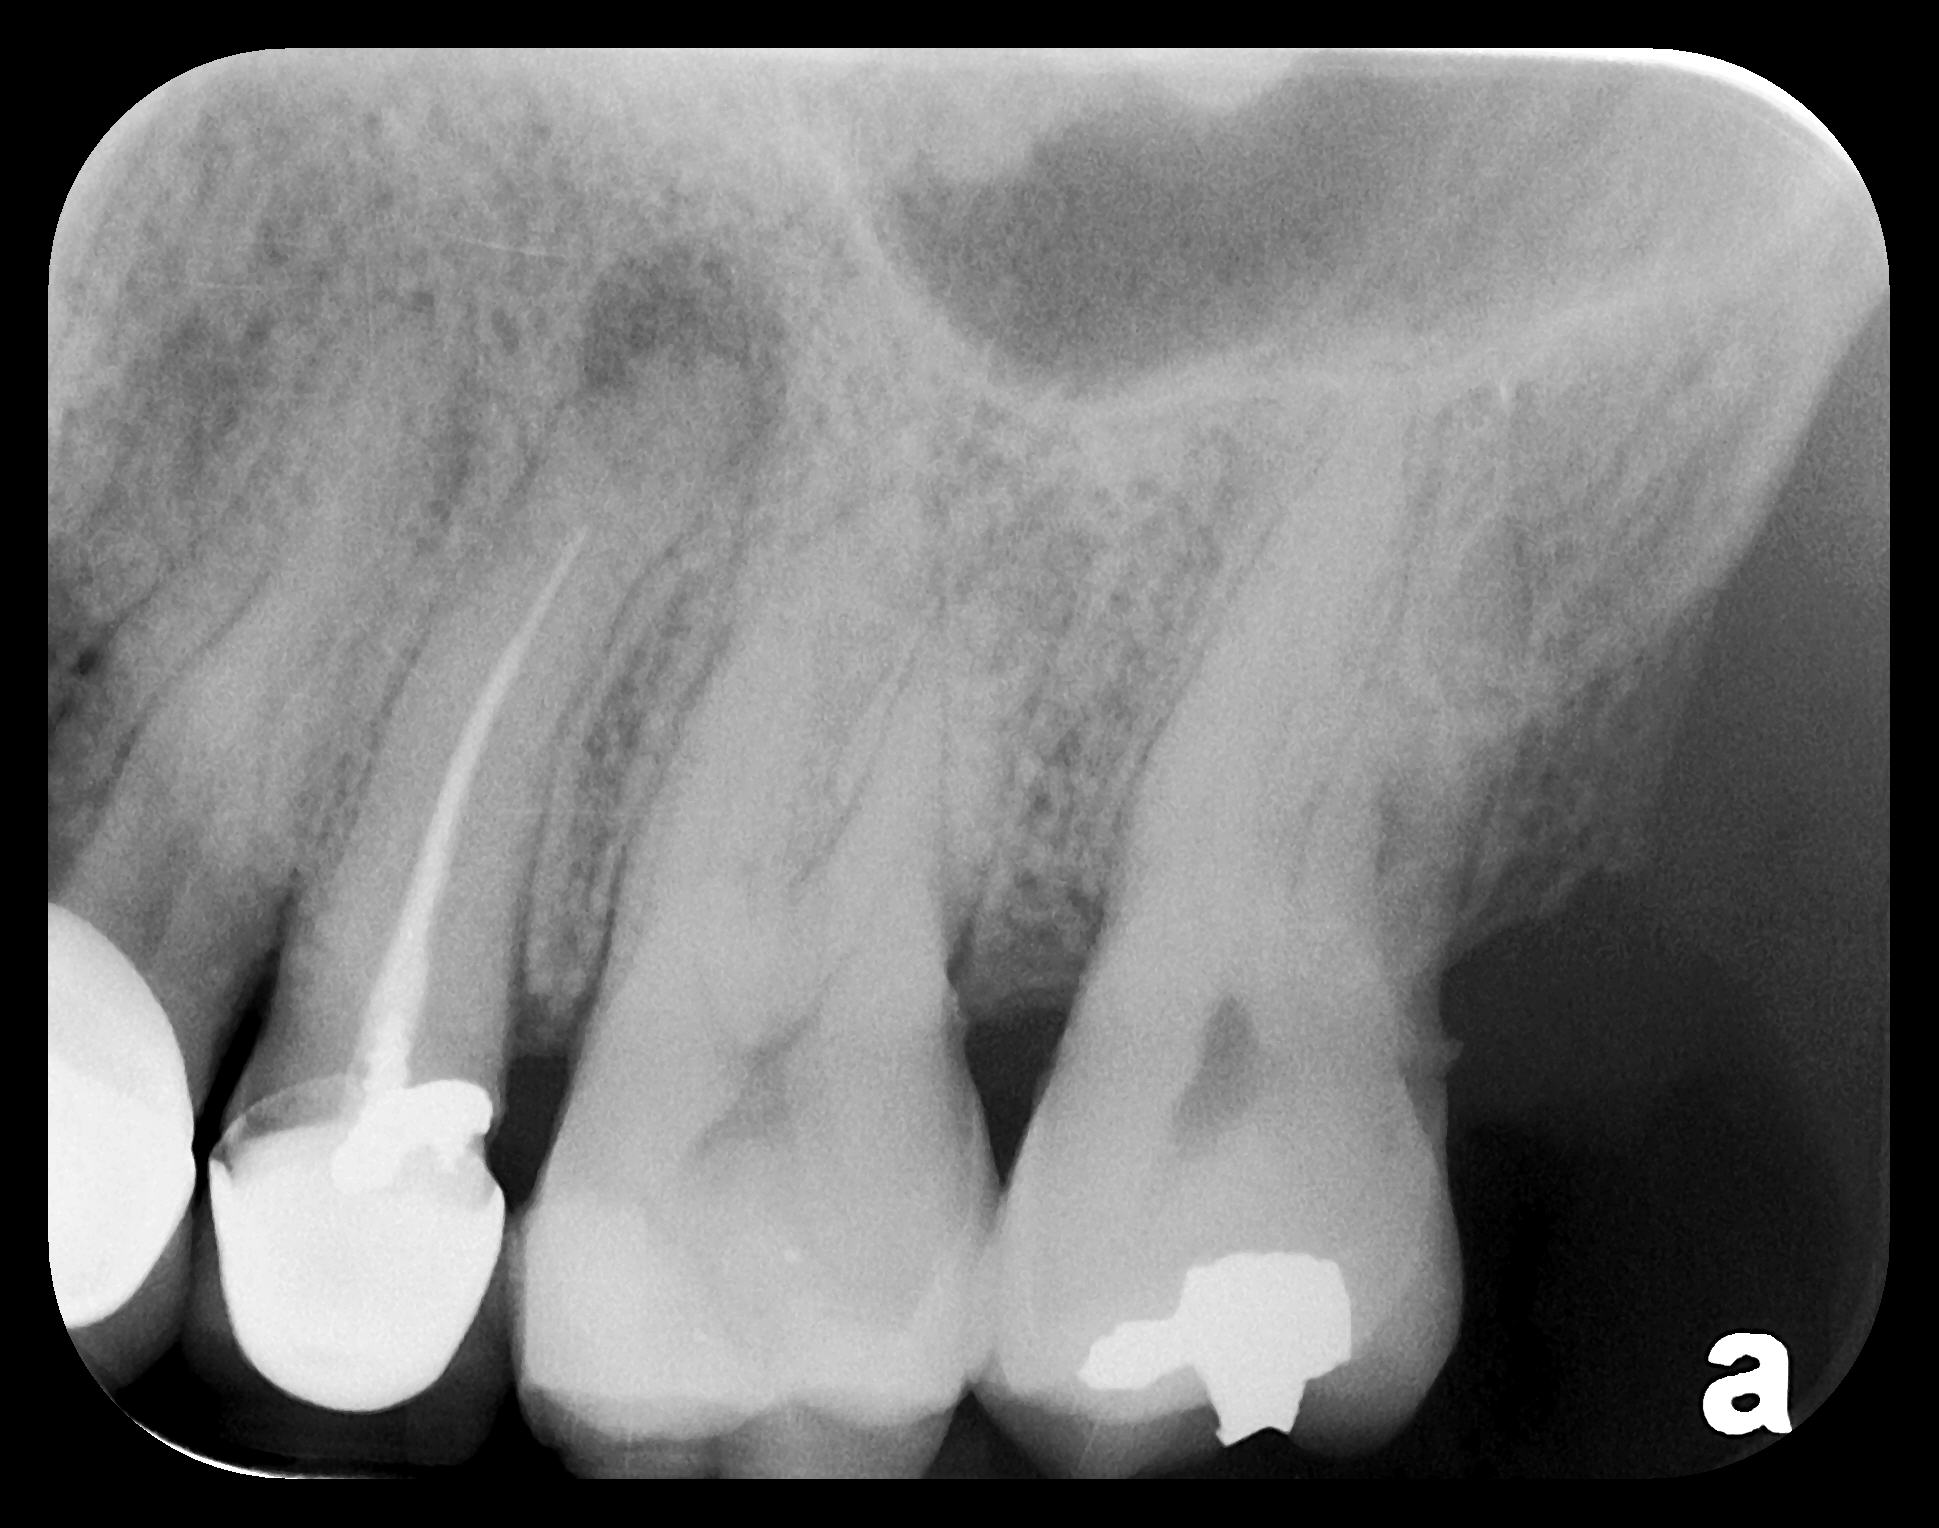

As displayed here, the 2D radiographic images in Figure 3 through Figure 8 can alert the clinician to the need for a further 3D CBCT analysis to properly ascertain the anatomy and extent of the pathology that is initially visible in the intraoral radiographs. Proper treatment or referral to the appropriate specialty practice can follow.5,6 No. 2 PSP radiographs, when used in a conventional full-mouth series of radiographs on a patient with a relatively complete dentition, will routinely allow visualization of the anatomy of third molars, mandibular canal, maxillary sinuses, full dental root morphology, and bone anatomy beyond the apices2,16,17 (Figure 9 and Figure 10).

Fig 9. Endodontic obturation overfill visible on PA radiograph, which is

escaping the apex of tooth No. 14 and extruding into the left maxillary

sinus. A pathologic sinus congestion, in the form of a slight radiopacity

within the sinus, is noted in response to the foreign material.

Figure 9